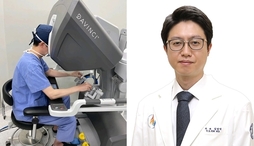

인하대병원 김경덕 교수, 인천 최초 다빈치SP 담낭절제술 성공